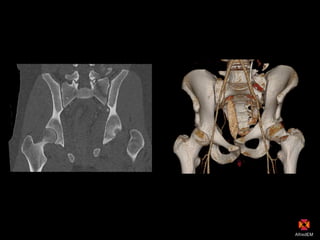

SIJ disruption + fracture

CT scan